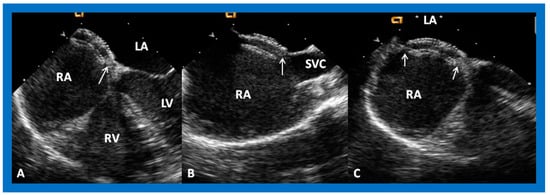

6. TEE and ICE

- Hellenbrand, W.E.; Fahey, J.T.; McGowan, F.X.; Weltin, G.G.; Kleinman, C.S. Transesophageal echocardiographic guidance of transcatheter closure of atrial septal defect. Am. J. Cardiol. 1990, 66, 207–213. [Google Scholar] [CrossRef]

- Singh, G.K.; Marino, C.; Rao, P.S. Ultrasound as an adjunct to cardiac intervention in the pediatric patient. J. Invasive Cardiol. 1996, 8, 341–349. [Google Scholar] [PubMed]

- Hijazi, Z.M.; Wang, Z.; Cao, Q.L.; Koenig, P.; Waight, D.; Lang, R. Transcatheter closure of atrial septal defects and patent foramen ovale under intracardiac echocardiographic guidance: Feasibility and comparison with transesophageal echocardiography. Cath. Cardiovasc. Interv. 2001, 52, 194–199. [Google Scholar] [CrossRef]

- Pedra, C.A.C.; Pedra, S.R.F.; Esteves, C.A.; Cassar, R.; Pontes, S.C.; Braga, S.L.N.; Fontes, V.F. Transcatheter closure of secundum atrial septal defects with complex anatomy. J. Invasive Cardiol. 2004, 16, 117–122. [Google Scholar] [PubMed]